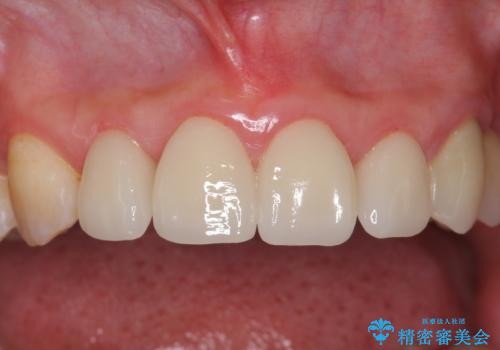

下の前歯との距離(クリアランス)が大きくは取れなかったため、ジルコニアクラウンではなくe-maxクラウンにしました。

また、歯ぎしりでセラミックがかけるのを防ぐために、就寝時にはナイトガードを装着してもらっています。

- 37万円(左上4:e-max クラウン 7万円x4、仮歯 1万円x4 右上2ファイバーコア:2万円x1 プレミアムナイトガード 3万円) 矯正治療は別費用は治療当時の料金となります